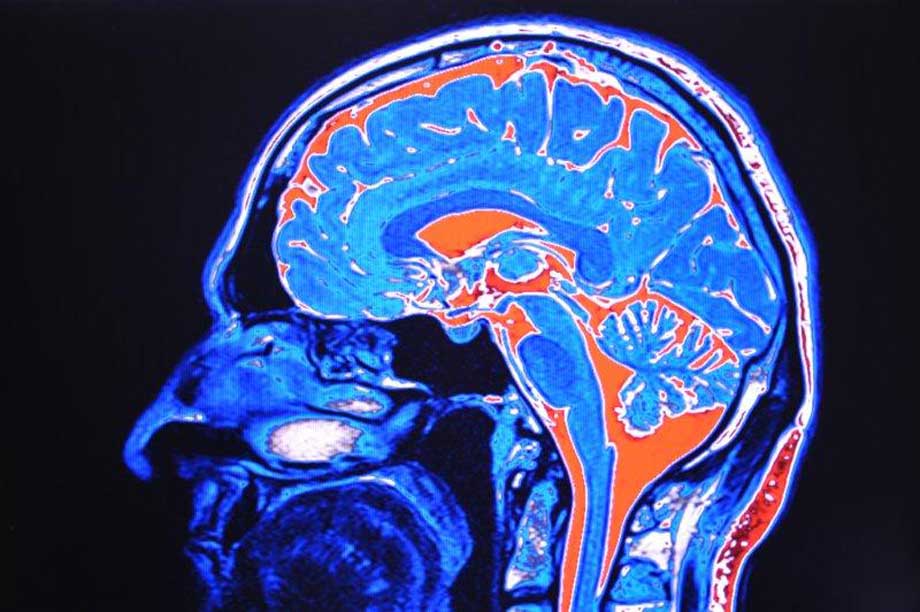

Paracetamol stört Entwicklung fötaler Stammzellen

Paracetamol stört Entwicklung fötaler Stammzellen 3sat nano: Video-Beitrag zum Thema Das könnte Sie auch interessieren: Paracetamol: Aktuelle Warnung vor der Einnahme in der Schwangerschaft Paracetamol, Schwangerschaft, ADHS, Entwicklungsstörungen Hamburg (Oktober 2014). Das frei ...